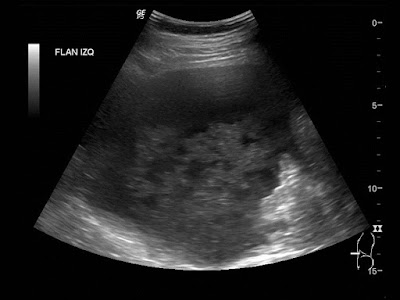

Paciente de 12 años con dolor abdominal. Remitida para estudio de masa intraabdominal.